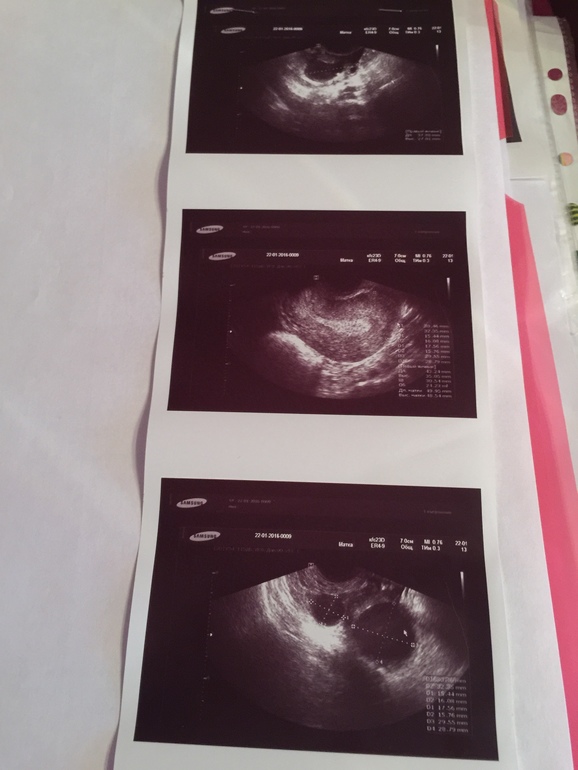

чтобы исключить полип в матке ( сегодня 5дц) . Полипа не нашла , но нашла кисту желтого тела . Вобщем предложила мне врач уже сделать лапару , посмотреть что и как и заодно удалить кисту если не уйдёт . Впринципе я уже давно хочу на лапару , чтобы все стало ясно хоть , а то 3 года , даже чуток побольше и результата никакого. Девочки , кто делал лапару в Москве или МО платно? Сколько стоит примерно ? Мне врач посоветовала к Слободяняку А.И в г.Жуковском. Никто не слышал про него? Или посоветуйте кто вам делал! Буду признательна !

Кстати , в этом мы тоже похожи...... У меня на 5 дц эндометрий уже 7.2 , мне кажется уже большой

Спасибо Алена! Так я же и пишу на 5 дц не увидели полипа, Гсказала , что , к сожалению, не всегда его видно на УЗИ, у многих только на гистере находят . ГСГ постараюсь сделать. Вот она нашла вроде киста жёлтого тела но поставила под вопросом , это она типа сомневается? И у меня вот теперь с этой стороны болит , сегодня 8 дц